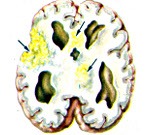

• КТ, МРТ головного мозга. Определяется утолщение, уплотнение оболочек мозга, диффузные изменения церебральных тканей. Наличие воспалительных очагов визуализируется не всегда. При паразитарной этиологии характерны округлые очаги гетерогенной структуры с кольцевидным усилением по периферии.